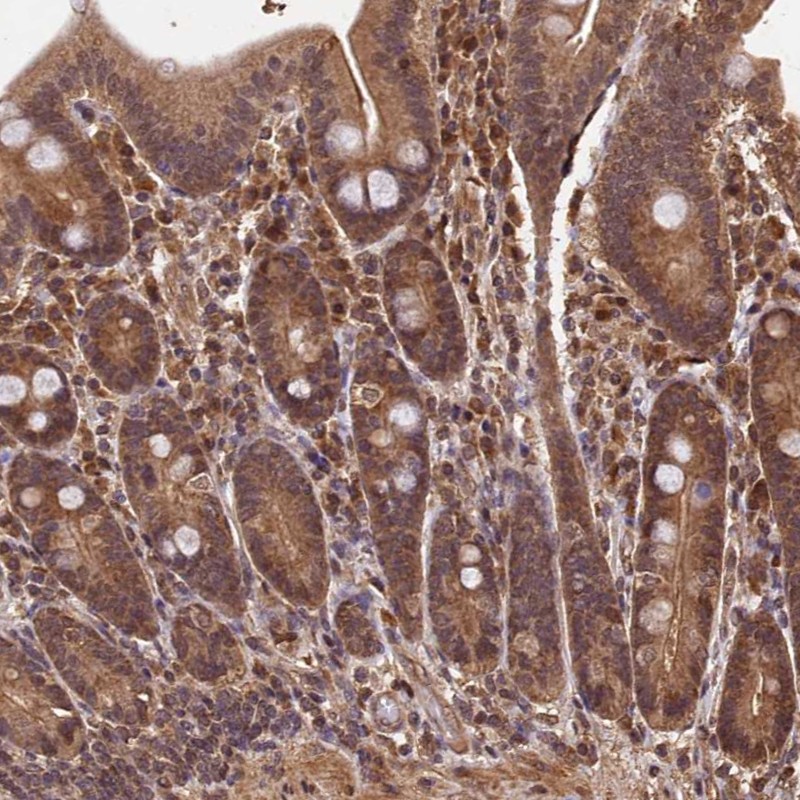

Immunohistochemical staining of human duodenum shows moderate cytoplasmic and nuclear positivity in glandular cells.